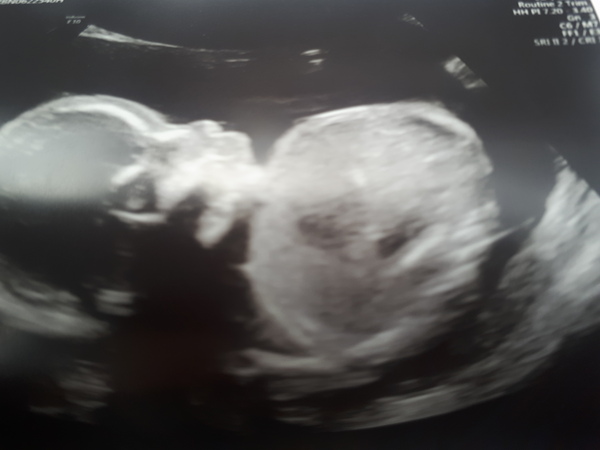

Baby girl!! All went well other than her standing on her head then being all scrunched up in a ball

Sj1989 lovely picture and congratulation *